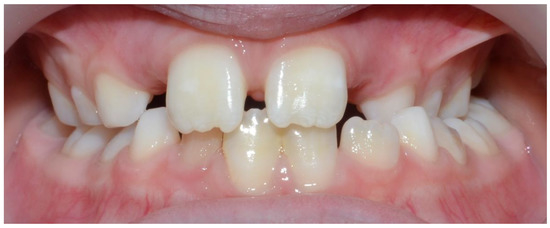

| Unilateral posterior crossbite—Right | 21 | - |

| Unilateral posterior crossbite—Left | 12 | - |